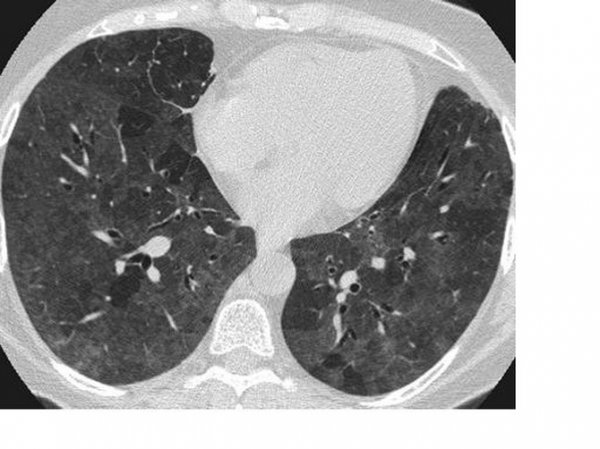

Naučni članak objavljen u Annals of Internal Medicine kaže da su snimci pluća asimptomatskih pacijenata pokazali određene abnormalnosti na plućima.

Tačnije, našli su ono što radiolozi nazivaju "mliječno staklo" koje se uglavnom javlja u donjem dijelu pluća, ali to ne mora uvijek da bude slučaj. Ovaj naučni tekst tvrdi da se "mliječno staklo" javlja u 54 odsto asimptomatskih pacijenata.

- "Mlečna pluća" nisu neuobičajena i postoji nekoliko uzroka za njih. Međutim, mliječno staklo nastalo usljed Kovida-19 je drugačije. Oblik je okrugao i raspoređeni su po krajevima pluća, što je neuobičajeno - kaže Adam Bernejm, radiolog iz Mount Sinai bolnice u Njujorku.